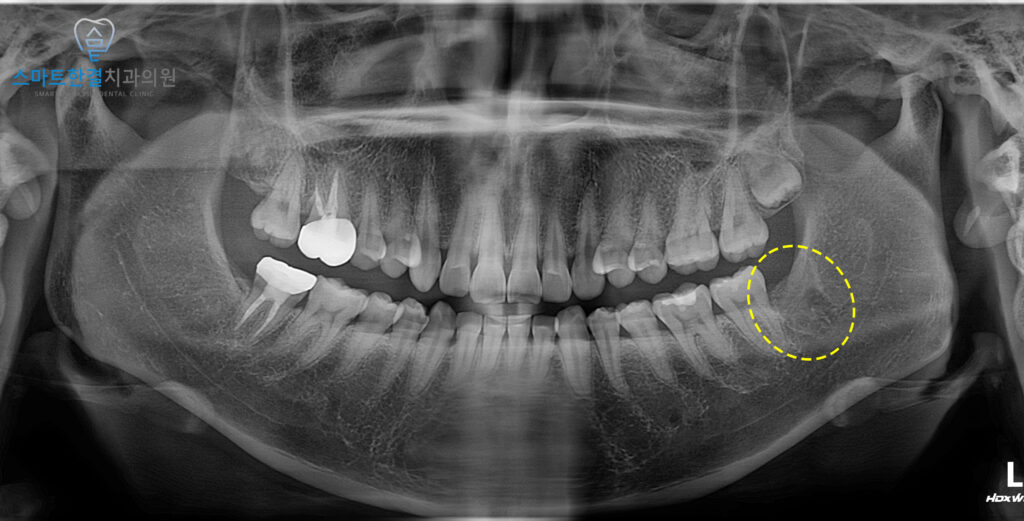

먼저 사랑니를 확인해 보니,

매복되어 있었고

뒤쪽으로 칫솔질 등 위생 관리가 어려워

잇몸에 염증 소견이 동반되어 있었는데요.

이로 인해 잇몸 부위의

부종과 불편감이 나타난 것으로

판단되었어요.

이 상태를 지속적으로 방치할 경우,

앞 치아에까지 영향이 갈 수 있어

발치가 필요했어요.